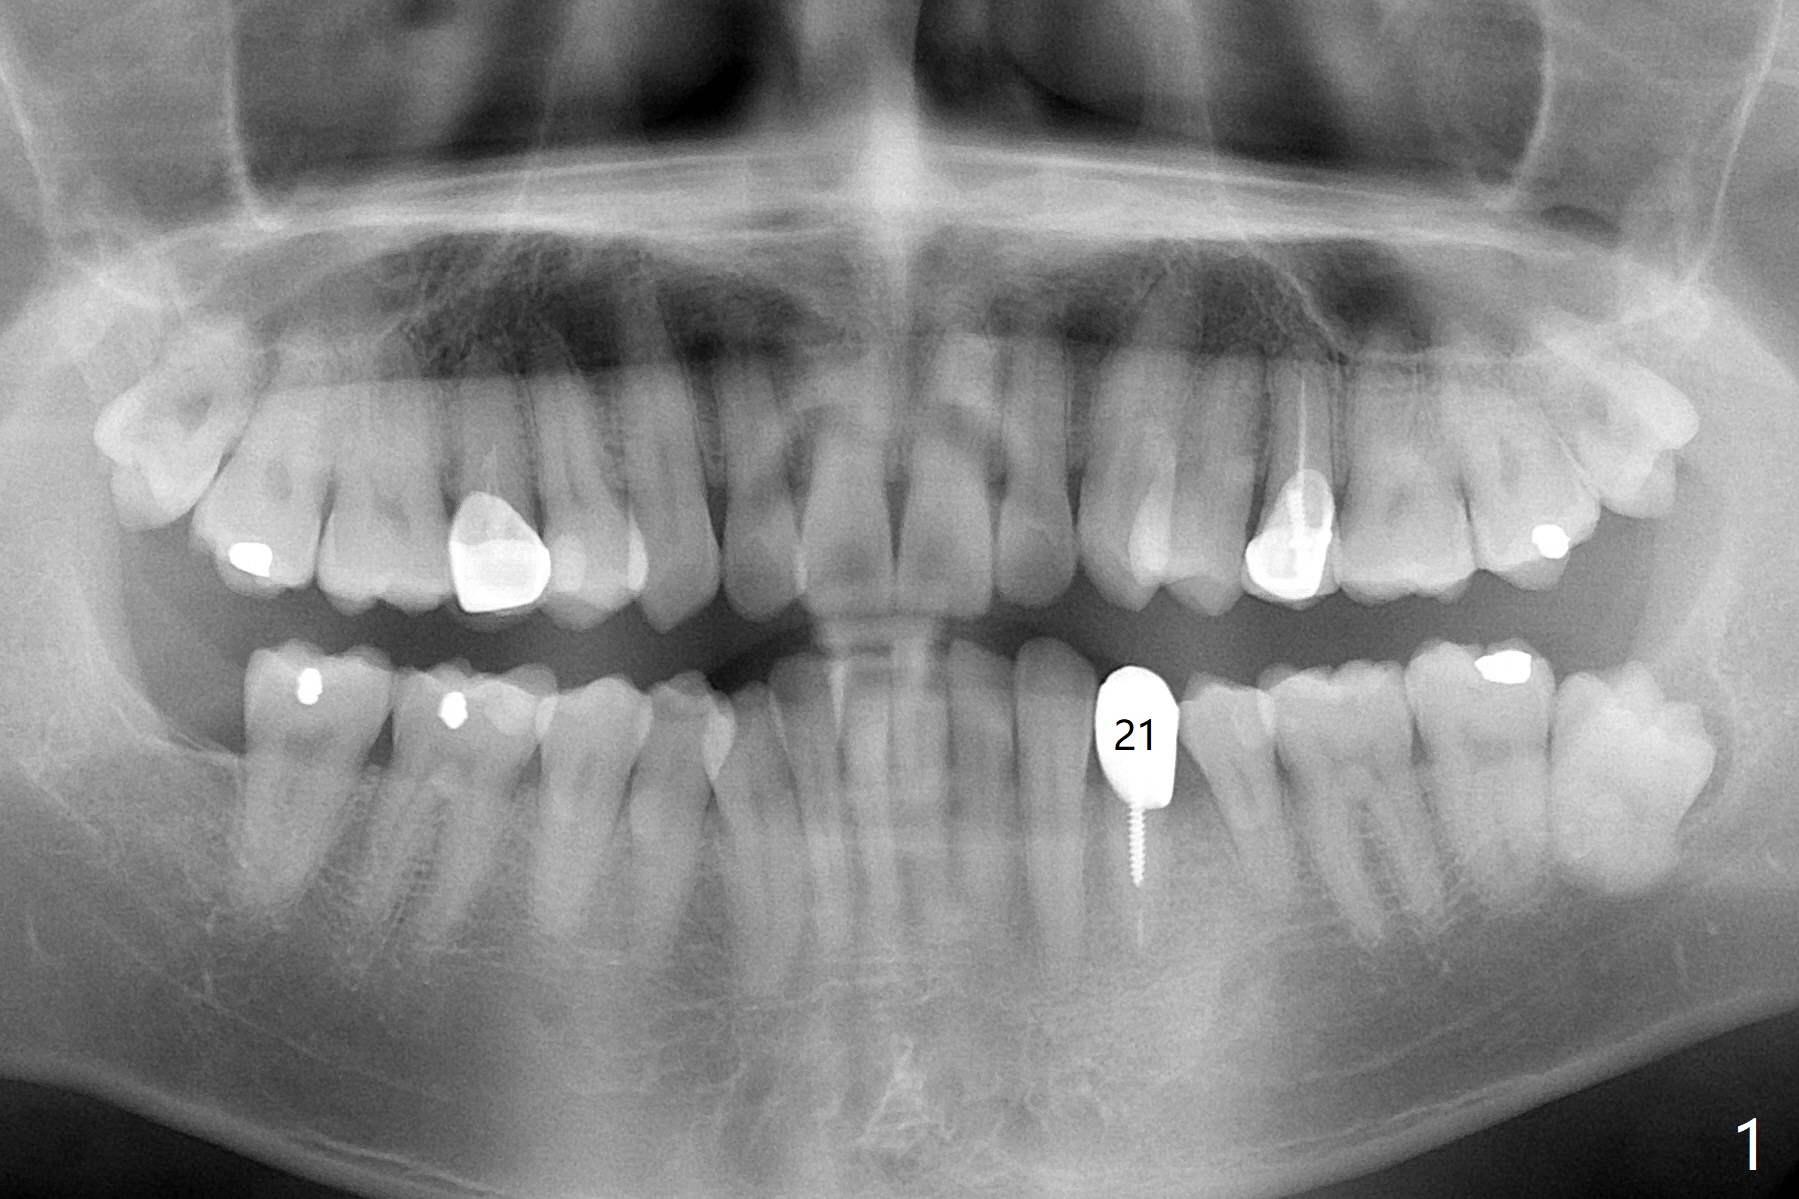

A 42-year-old man has been our patient for 3-4 years (Fig.1). An asymptomatic fistula develops lingual to the tooth #21 (Fig.2). An oblique fracture line appears to be next to a post (Fig.3 ^). A 3.5x11.5 mm implant seems to be able to be placed immediately lingual to the thick lingual plate with guide (Fig.4 L). No buccal deviation will occur with sufficient buccal gap. Design of an immediate implant at #21 (coronal section, Fig.5). In fact the root remains in place first (i.e., extract the crown first, Fig.5'). When osteotomy is done with the last drill 4x11.5 mm, there will be no deviation because of even counteraction between the buccal root and the lingual plate (Fig.6'). Then the root will be removed. But the 4.5x11.5 mm implant may be deviated buccal because of implant engagement into the lingual plate without buccal counteraction. Therefore, a 4x13 mm implant will be placed following 3.5x13 mm (last) drill. The implant is placed between the mesial and distal walls (Fig.7 sagittal section).